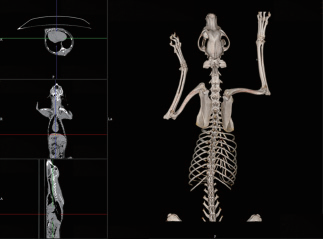

专业的宠物界面设计

专门为宠物设计的操作界面

动物登记界面,独有特色包含主人姓名,动物是否绝育、物种选择及近千种的品种选择等